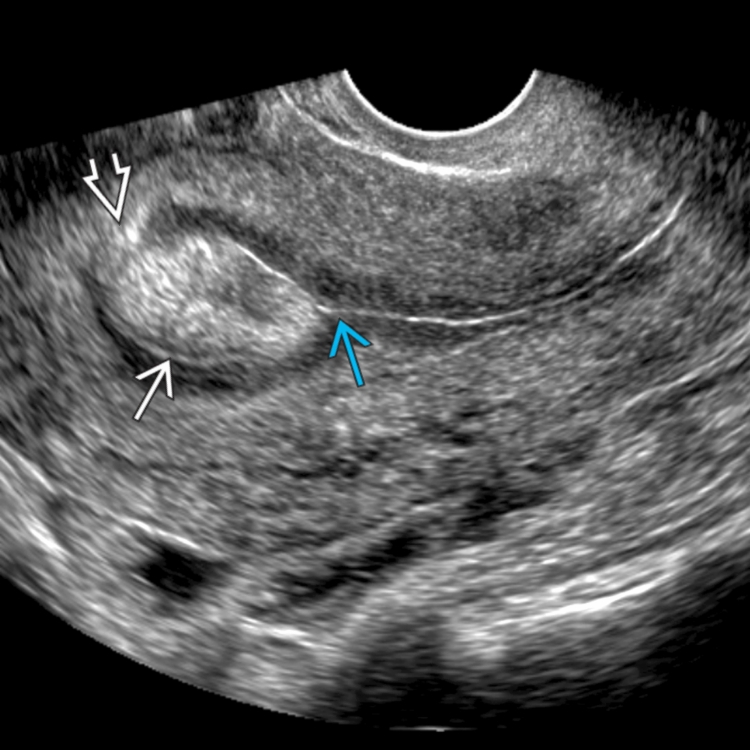

What pathology are we seeing in this image?

Gartner cyst